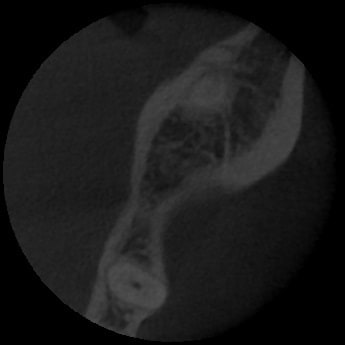

Lors de mon analyse scanner, je constate que au niveau de l'épaisseur crestale vestibulolinguale, je suis tout à fait a l'aise pr poser un 5x11,5mm.

En revanche, sur les 2 premiers millimétres de hauteur (au niveau cortical) , je n'ai pas 8mm en vestibulolinguale, comme il faudrait pr être bien pour poser un 5mm, mais j'ai tout juste 5mm (à peine)... La crête est en fait plus fine tout en haut de la crête, ce qui est je pense assez commun, puisque après l'extraction très ancienne, l'os s'est remodelé donnant cette petite lame de couteau (quand même épaisse d à peine 5 mm donc...)

Voici les photos

Épaisseur de crête au niveau du trait rouge.